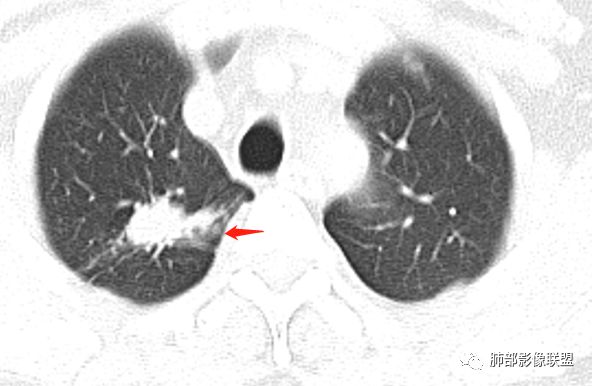

影像,气管憩室,两肺尖都有病灶,长索条

右肺上叶病灶两部分

纵隔窗提示内侧部分密度不够实

边缘平直、凹陷为主,部分膨隆

内部小点状影提示可能支气管腔内粘液栓

左肺尖及右肺病灶附近见小斑点,边界尚清

1、病灶整体形态不是类圆形,边缘凹陷、平直为主,长轴重建可能更明显,长索条,附近卫星灶,左肺尖有类似小高密度影;按常规:首先要考虑结核

结果:结核合并真菌(曲霉菌)感染